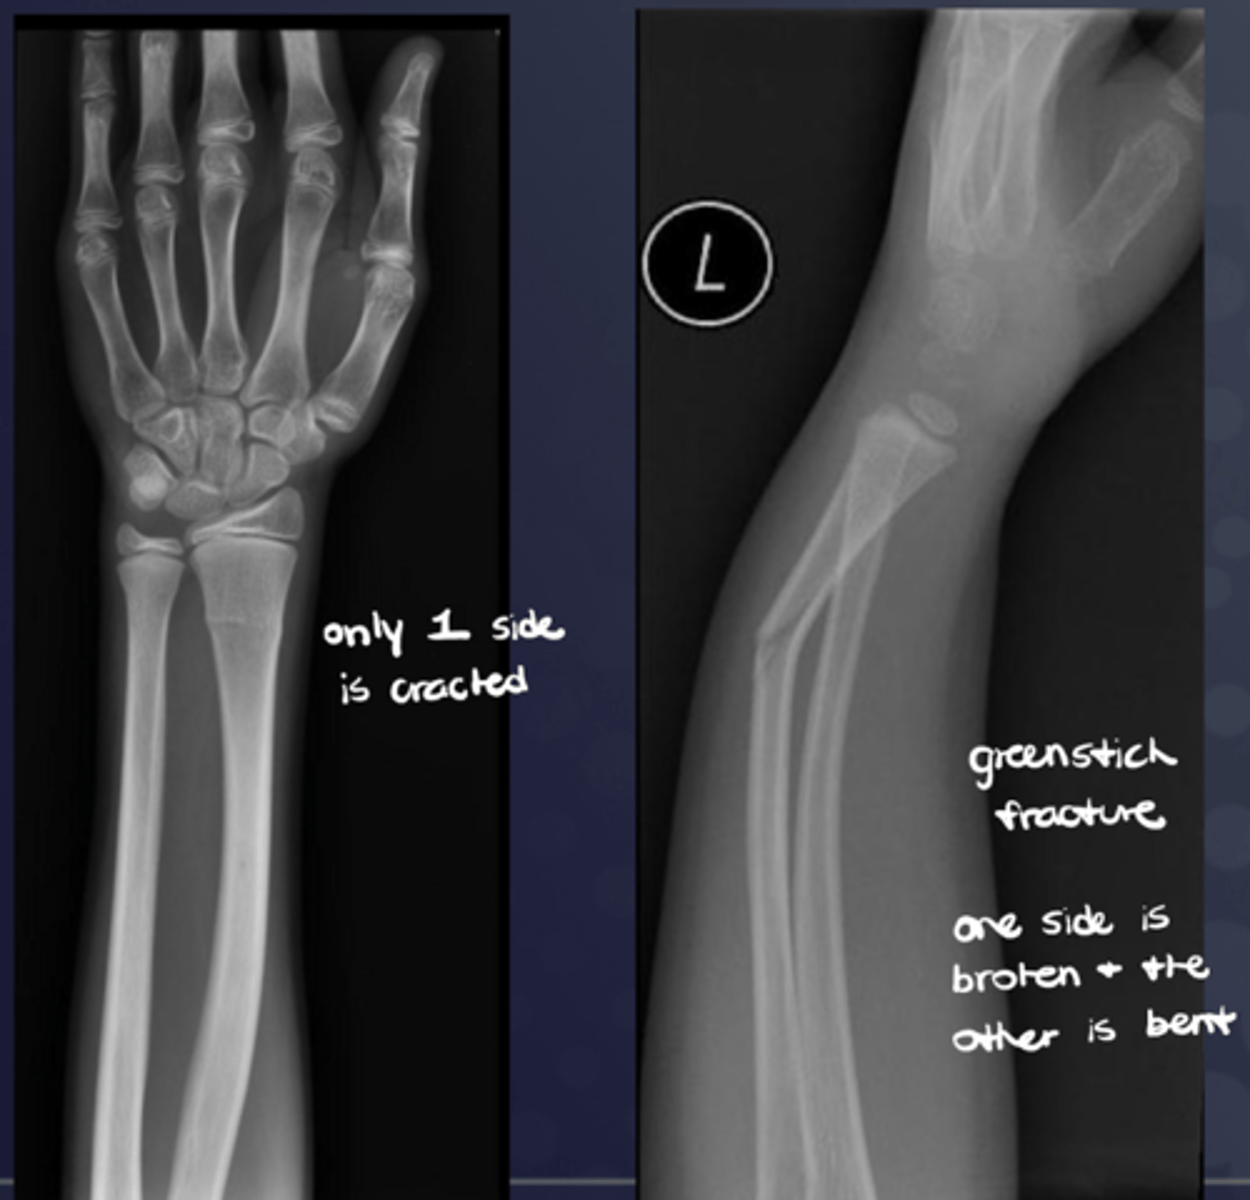

What is an "incomplete" fracture?

Fracture "hinges" on an unbroken cortex (e.g., "greenstick fracture" in immature bone)

What is a "buckle" fracture?

Incomplete bone break where one side of the bone bulges or "buckles" under pressure, without the bone completely snapping in two, usually occurring in children due to their softer bones that bend more easily than adults' when force is applied